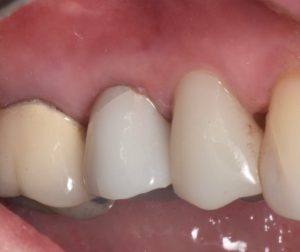

This video demonstrates a fully guided immediate implant placement protocol following premolar extraction, combined with immediate provisional restoration. The case highlights a digitally driven workflow designed to enhance accuracy, efficiency, and prosthetically guided implant positioning.

Step-by-step, the procedure covers atraumatic tooth extraction, guided implant placement using a surgical guide, and chairside fabrication and delivery of an immediate provisional restoration. Clinical considerations for achieving primary stability, soft tissue preservation, and optimal emergence profile are emphasized to support predictable esthetic and functional outcomes.